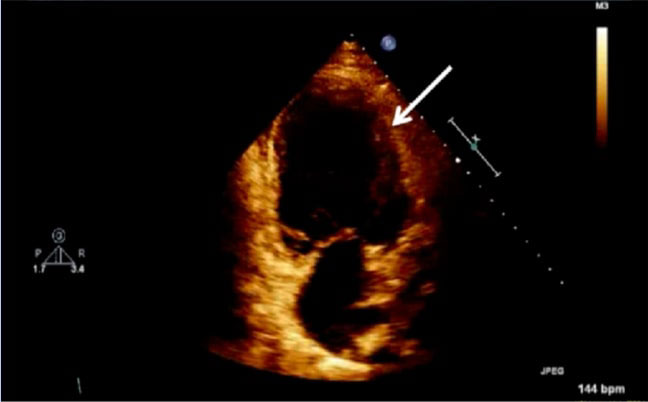

The exemption from the Institutional Review Board of Cleveland Clinic and consent from the patient were obtained for our case. A 42-year-old obese (body mass index 37.6 kg/m2) female at 38w2d, G2P1 with past medical history significant for gestational diabetes mellitus, presented with a three-day history of shortness of breath, orthopnea, chest tightness, tachycardia, headache, and swollen feet. She denied fever, vision changes, and right upper abdominal pain. No history of cardiac diseases or chronic hypertension was reported. Her vital signs included blood pressure (BP) of 145/98 mmHg, respiratory rate of 30 breaths per minute, heart rate of 150 beats per minute (bpm), and blood oxygen saturation (SpO2) of 98% on 10 liters per minute of oxygen through a non-rebreather mask. She was afebrile. Physical exam revealed loud S3 gallop, bilateral basilar rhonchi, and bilateral feet and ankle edema. Fetal monitoring was normal with a heart rate of 125 bpm. Laboratory results showed a white blood cell count of 12.8 k/µL, urine protein of 74 mg/dl, NT-proBNP of 1017 pg/ml, mildly elevated aspartate transaminase of 45 U/L and alanine transaminase of 30 U/L, and normal troponin. Electrocardiogram reported sinus tachycardia with borderline LV hypertrophy and frequent premature ventricular contractions (PVCs). Chest X-ray showed bilateral basilar infiltration. Echocardiogram revealed dilated LV with severely decreased function, EF of 25%, diffuse LV hypokinesia, and normal right ventricle function (Figure 1 and Figure 2). The patient started contractions and labor analgesia was administered through the epidural catheter; BP was noted to be 118/62 mmHg. Coagulation profile was normal. She was admitted to the intensive care unit (ICU) and Swan Ganz catheter, central, and arterial lines were inserted to monitor hemodynamics and heart function. Although our patient's clinical symptoms may lead us to consider preeclampsia, we ruled out preeclampsia because her labs did not meet criteria for diagnosis. Our patient was diagnosed with PPCM, for which she was placed on intravenous (IV) furosemide, tocolytic medication, and digoxin. Tocolytic medication was given to delay delivery until heart function improved, as the patient was unable to lie flat and EF was very low.

Figure 2: Echocardiogram of apical four chamber view of the heart, depicting left ventricular wall hypertrophy (white arrow).